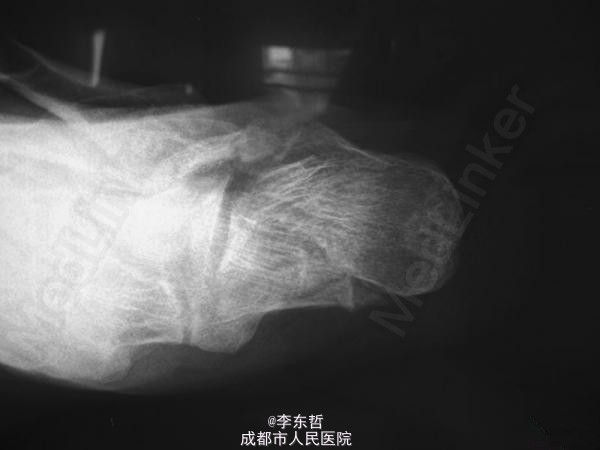

左足跟骨骨折

跟骨骨折

患者男性,60岁;高处坠落致左跟部肿痛10天入院,查体示左跟部略肿,压痛,无皮裂出血;予刚针撬拨术复位。